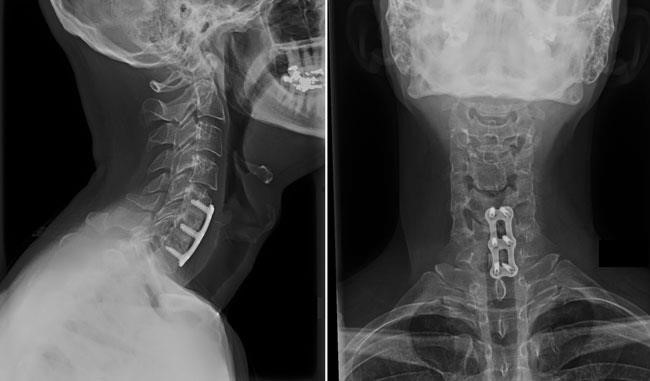

2. Anterior Cervical Discectomy and Fusion (ACDF)

ACDF is the most commonly performed procedure to treat cervical radiculopathy. The procedure involves removing the problematic disc or bone spurs via an anterior (front of neck) approach and then stabilizing the spine through spinal fusion.

The goals of ACDF are to restore alignment of the spine, maintain or enlarge the space available for the nerve roots to leave the spine, and limit motion across the degenerated segment of the spine.

The "anterior" approach is performed through a 4-5cm incision along the neck crease, most safely done on the left side of the neck. The relevant level is confirmed with intra-operative X-ray control. The problematic disc and any additional bone spurs are removed, the disc space is restored to the height it was prior to the disc wearing out, and this creates more room for the nerves to leave the spine and aids in decompression. A spinal fusion is used to stabilize the spine, with the basic concept being to fuse together the vertebrae so that they heal into a single, solid bone. Fusion eliminates motion between the degenerated vertebrae and takes away some spinal flexibility. The theory is that if the painful spine segments do not move, they should not hurt. A metal or plastic spacer (or cage) filled with bone graft (or combined with synthetic bone graft substitute) is impacted into the defect prepared after removal of the old disc, and supplemental fixation in the form of a plate and screws is also added.

orthoinfo.aaos.org

An anterior cervical discectomy and fusion from the side (left) and front (right). Plates and screws are used to provide stability and increase the rate of fusion.